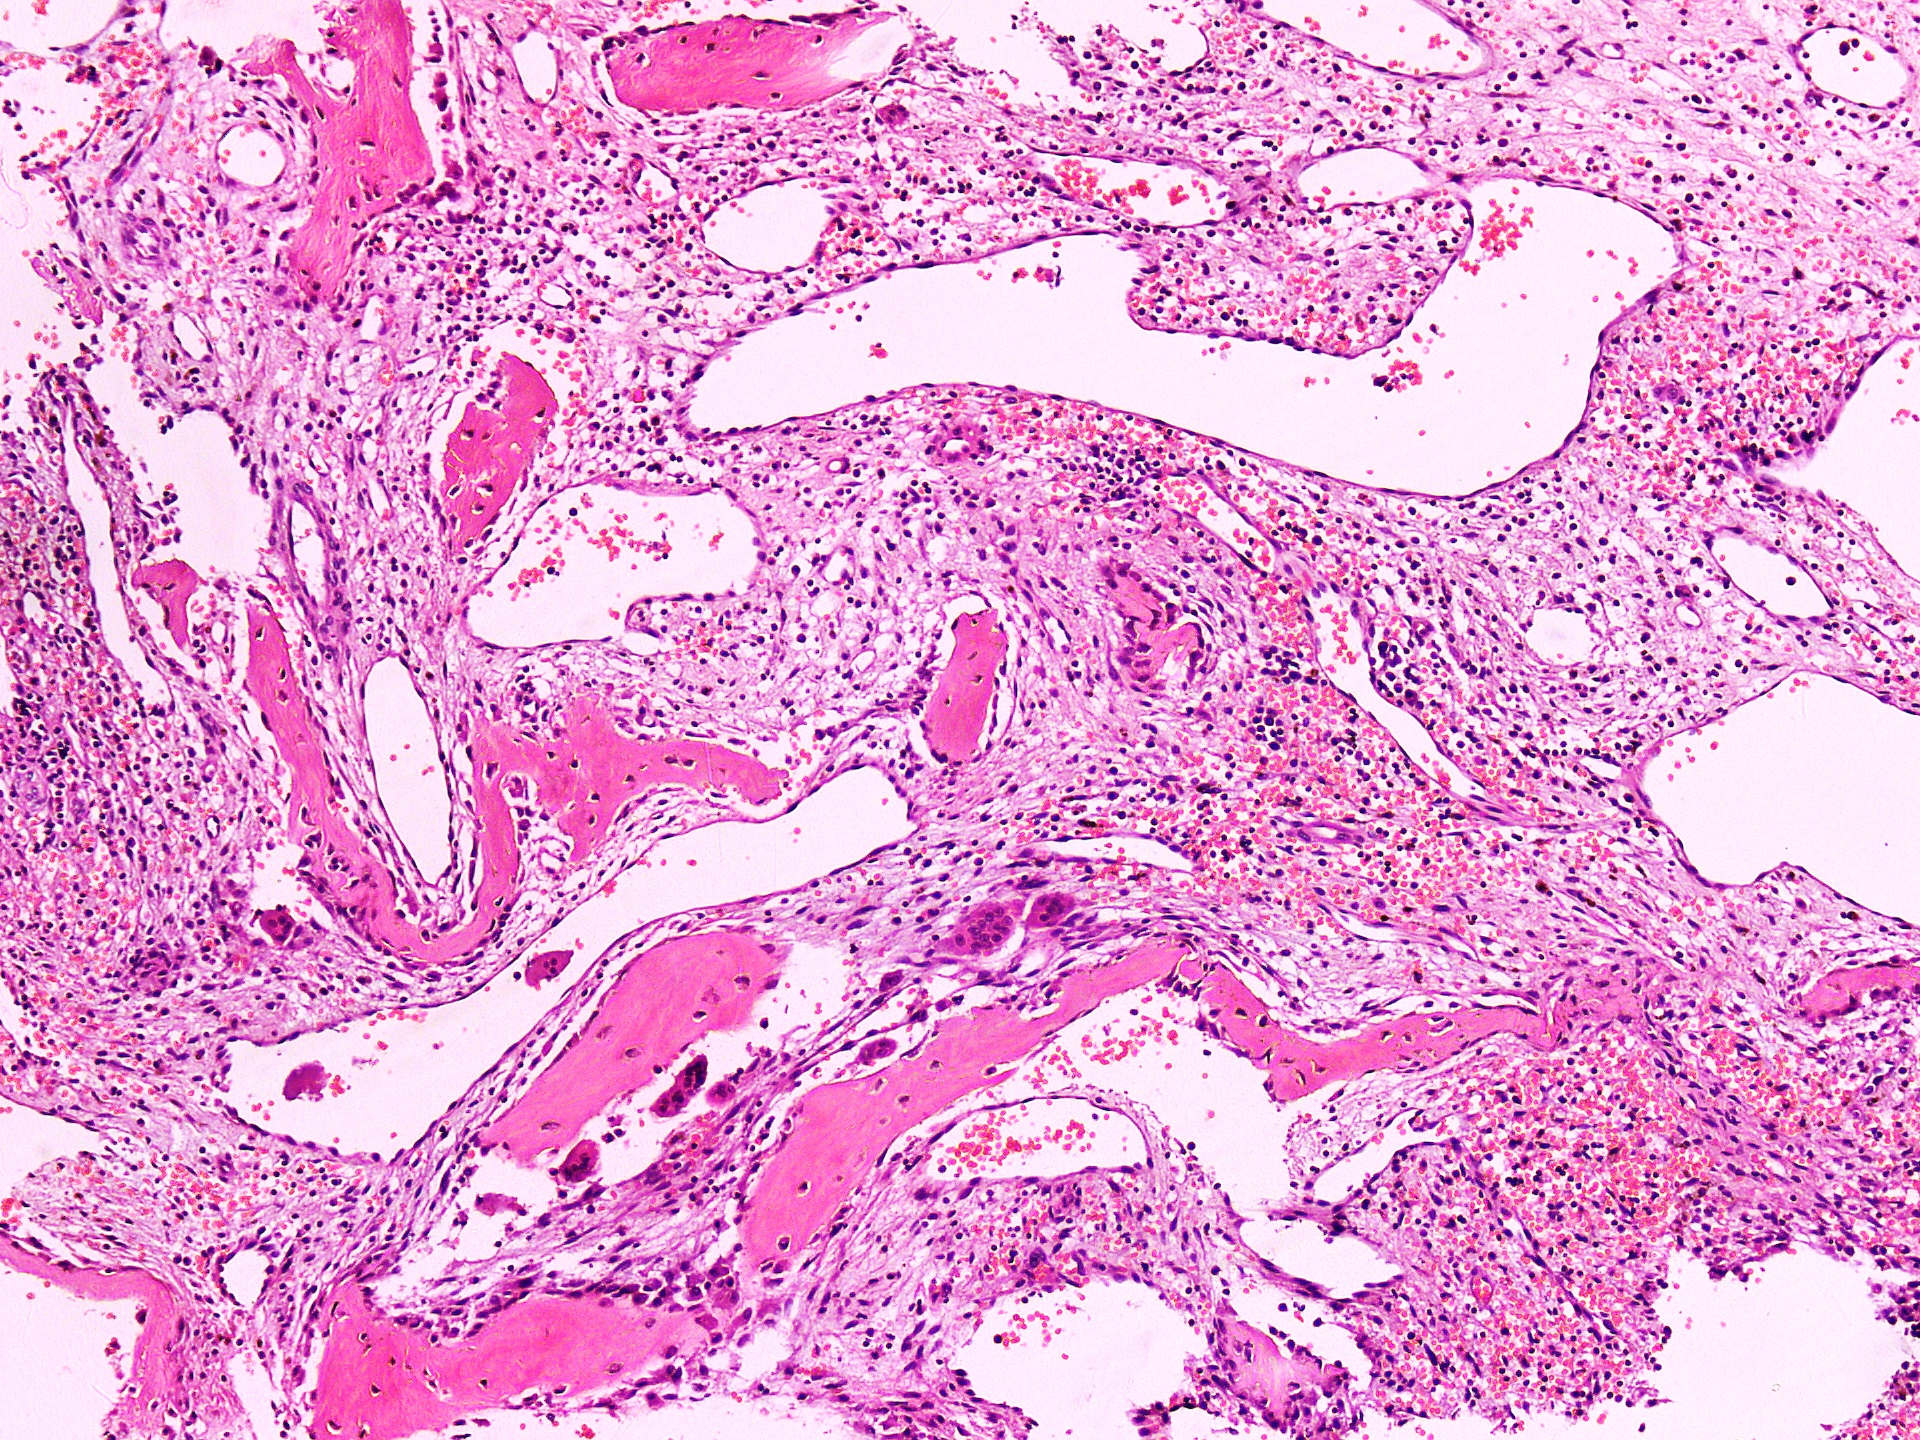

Gross description

- Spongy brown cystic hemorrhagic lesion

Microscopic (histologic) description

- Lobular pattern composed of groups and clusters of osteoclast-like multinucleated giant cells

- Vascular fibroblastic stroma

- Hemorrhage and hemosiderin deposits

- Tunneling resorption of adjacent uninvolved bone (J Int Oral Health 2015;7:50)

Microscopic (histologic) images